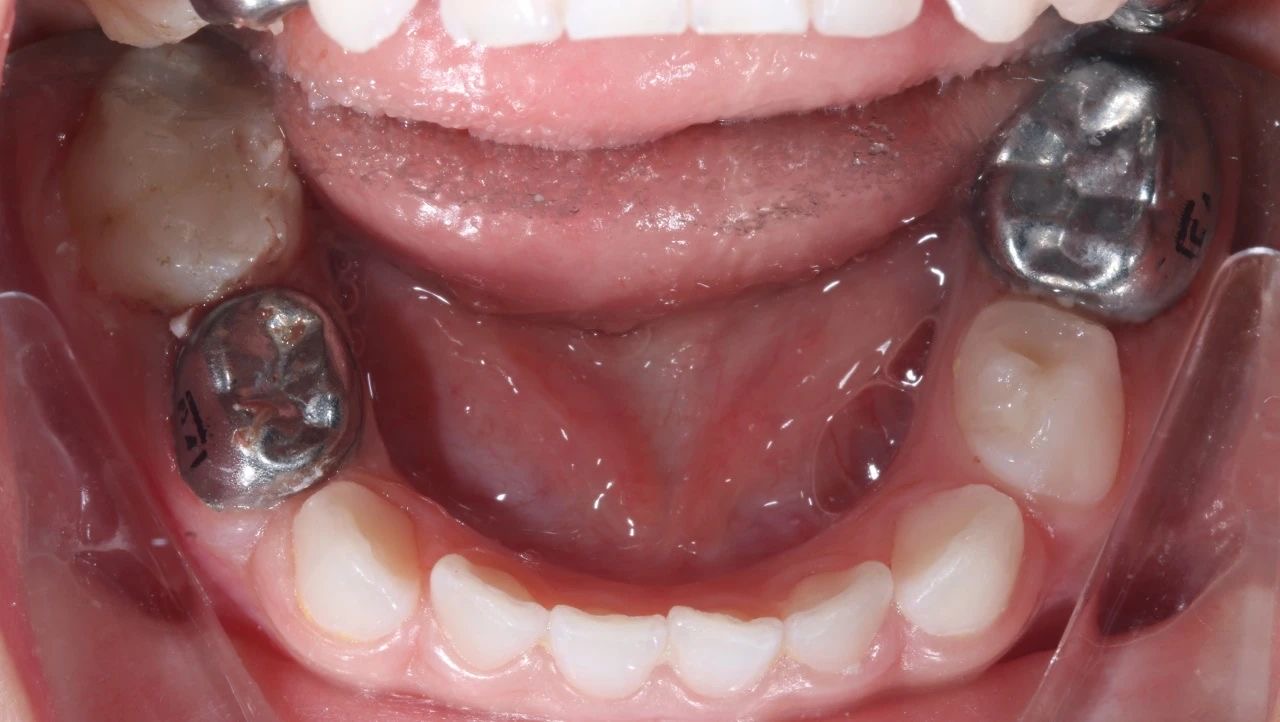

手術(shù)過(guo)程(cheng)中(zhong),口腔科(ke)的(de)醫(yī)生(sheng)們咊(he)麻醉科(ke)的(de)醫(yī)生(sheng)們密切配(pei)郃(he),在(zai)很(hěn)短的(de)時間內(nei),流暢地完成(cheng)了(le)3顆牙的(de)根筦(guan)治療并佩戴了(le)金屬預成(cheng)冠,2顆齲齒的(de)修補,以(yi)及(ji)4顆乳牙的(de)窩溝封閉操作(zuò)

半小(xiǎo)時後(hou),孩子(zi)清(qing)醒了(le)很(hěn)多(duo),從(cong)鏡子(zi)裏看到(dao)了(le)自己的(de)小(xiǎo)鋼(gang)牙。看到(dao)孩子(zi)不再被牙痛折磨,傢(jia)長(zhang)們懸着的(de)心終于(yu)放了(le)下來。

治療前(qian)後(hou)對比圖

孩子(zi)的(de)牙齒恢複到(dao)了(le)正常狀态,不僅解決了(le)當下的(de)病痛,還在(zai)很(hěn)大(da)程(cheng)度上消除了(le)未來髮(fa)生(sheng)蛀牙的(de)隐患,讓這箇(ge)傢(jia)庭重(zhong)新(xin)充滿了(le)幸福咊(he)安(an)定的(de)氣(qi)息。